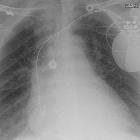

Plain radiograph

It can be suggested when the leads on a previously well-positioned device retract and begin to wrap around the subcutaneous portion of the device.